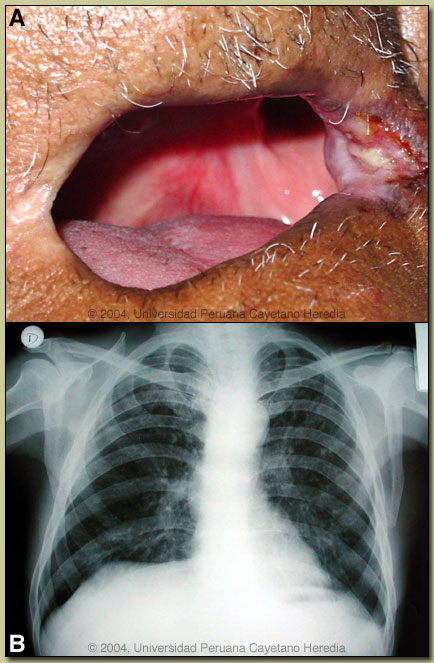

| Diagnosis: Paracoccidioides brasiliensis infection (chronic form). |

Discussion: Direct sputum examination with KOH showed P. braziliensis yeast forms with single budding. This deviation, from the typical pilot-wheel shaped organisms consisting of spherical cells 10-40 microns in diameter with a thick birefrigent cell wall surrounded by several peripheral buds, may have been caused by the prior sulfa treatment. The culture incubated at room temperature is negative so far but the filamentous forms may take up to 45 days to grow. A biopsy of the lip lesion [see image C] showed granulomas with multinucleated giant cells containing yeast forms of P. braziliensis (PAS stained; see arrow and boxed area in image).

The differential diagnosis for the lung disease includes: TB, histoplasmosis, lymphoma, cancer and cryptococcosis. The oral lesions must be differentiated from mucocutaneous leishmaniasis, TB, histoplasma, and malignancy. In general, oral lesions of paracoccidioidomycosis are painful while those of leishmaniasis are completely painless despite widespread destruction of tissue, and leishmania lesions rarely bleed. The lungs are the primary site of infection in paracoccidioidomycosis. In 30% of patients, lungs are the only organs affected, but in necropsy studies over 90% of all patients have pulmonary involvement. A characteristic clinical feature (also seen in this patient) is the dissociation between clinical symptoms and the degree of pulmonary involvement. The most typical radiographic pattern is bilateral mixed infiltrates (alveolar and interstitial), mainly located in the middle and lower lobes. Interstitial lesions may have a miliary, nodular or fibronodular patterns. This patient does not differ much from the typical pattern, although he has more upper lobe disease than expected. Other patterns observed in these patients are hilar and mediatinal lymph node enlargement, cavities, and calcified lesions. Patients with oral and skin lesions may not have respiratory symptoms, but almost always have pulmonary involvement. Extrapulmonary disease is found in over 70% of cases and may involve skin, mucous membranes, lymph nodes, adrenals, abdominal organs and CNS (in 10%). Bacterial superinfection of ulcerative lesions is more common that with oral ulcers due to mucocutaneous leishmaniasis. This case is representative of the chronic form (adult type) of the disease, which is believed to represent reactivation of latent infection. This type represents approximately 94% of all cases in the experience at our institute (94 patients, up to 2001), and approximately 85% in the Brazilian series (Rev Soc Bras Med Trop 2003;36:455-9). In our experience the male:female ratio in chronic paracoccidioidomycosis is 20:1. TB coexists in up to 10% of patients with paracoccidioidomycosis. Cavitation and pleural effusion are less commonly seen than in TB. Paracoccidioidomycosis, also known as South American blastomycosis is found in humid forested or lush green areas of the Americas from Southern Mexico south to Uruguay and Argentina. It appears to be most common in Brazil. The exact habitat of the organism is unclear but transmission is described as being entirely by airborne inhalation. However, we have observed cases with only oral lesions apparently associated with the use of tree leaves contaminated with fungal spores as toothpicks. Similarly the use of leaves as toilet paper has resulted in anal infections that can be confused with anal cancer. Primary pulmonary infection may be asymptomatic and self-limited but even with treatment will produce at least moderate pulmonary fibrosis. Rural adult males agricultural workers between 30-60 years of age are most affected by the infection. Travelers spending less than 6 months in an endemic area are unlikely to acquire paracoccidioidomycosis. Sulfonamides, ketoconazole, itraconazole, and amphotericin B are all effective therapies. Amphotericin should be reserved for severe cases. While itraconazole 100 mg/day for 6 months or so is regarded as the treatment of choice, in the developing world setting ketoconazole is likely equally effective and is usually less than half the cost. However, 12 months of therapy with ketoconazole is generally recommended. Paracoccidioidomycosis is always a severe infection that may relapse even after prolonged treatment so always needs to be treated and followed up aggressively.